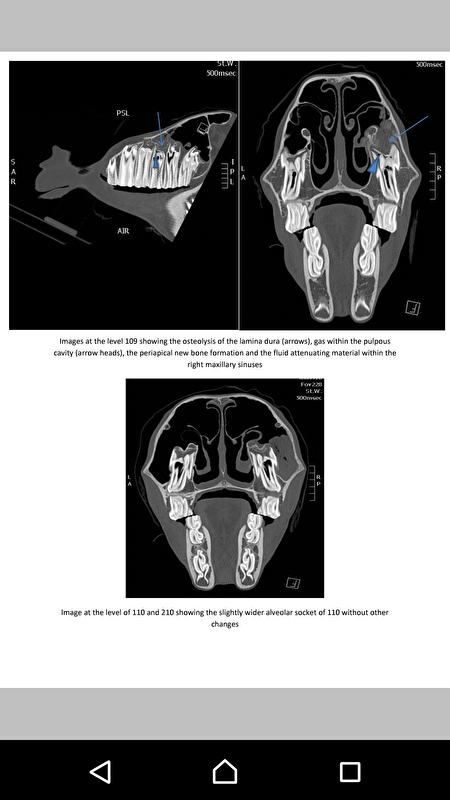

Hier recent een 'jong' paard, zeer slecht eten plotseling.

Hoewel niets op de foto's te zien toch een ct scan laten maken.

Wel kieswortelontsteking.

Afbeelding

Voor ons was de ct scan de enige optie.

Anders was het afwachten en eventueel later meer foto's maken, als de ontsteking verder ontwikkeld zou zijn of als het bot in de kaak aangevreten zou worden.

Ct scan kan staand in Utrecht.

Viel ons alles mee. Zeer duidelijk beeld in tegenstelling tot de laag over laag foto's.

Kosten externe ct scan, 450 euro inclusief alle sedatie e.d.